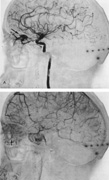

Tortuous or redundant basilar arteries are not uncommon in the older age group. Occasionally, gross dilation or ectasia develops so that the basilar artery acts as a mass in the posterior fossa. This phenomenon produces signs of low-pressure hydrocephalus, cranial nerve palsies, and long tract and sensory signs and may even simulate a cerebellopontine angle tumor or tumor at the foramen magnum.58 It is possible to diagnose such lesions with CT59 or MRI60 but angiography is definitive (Fig. 6). The association of insidious multiple cranial nerve palsies and long tract signs referable to a brainstem level, in an elderly patient with evidence of atherosclerosis, should make fusiform basilar artery dilation a diagnostic consideration.

Fig. 6. Fusiform basilar dilation. A: Lateral projection vertebral arteriogram showing a widened basilar artery (arrow) projecting beyond level of dorsum sellae. B: Anteroposterior projection showing a widened and tortuous basilar artery.